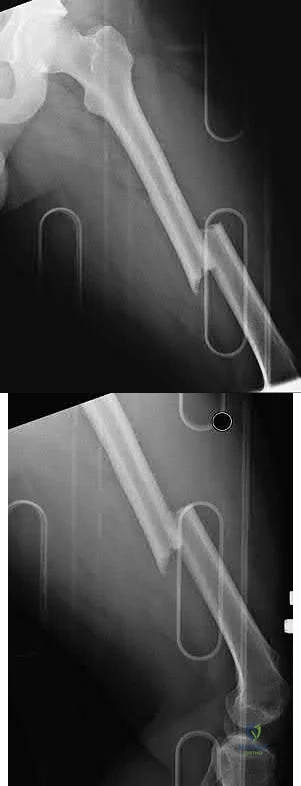

Figures A-D are radiographs demonstrating a femoral shaft fracture. Incorrect Answers:

Figures A and B are radiographs demonstrating a transverse femoral shaft fracture.